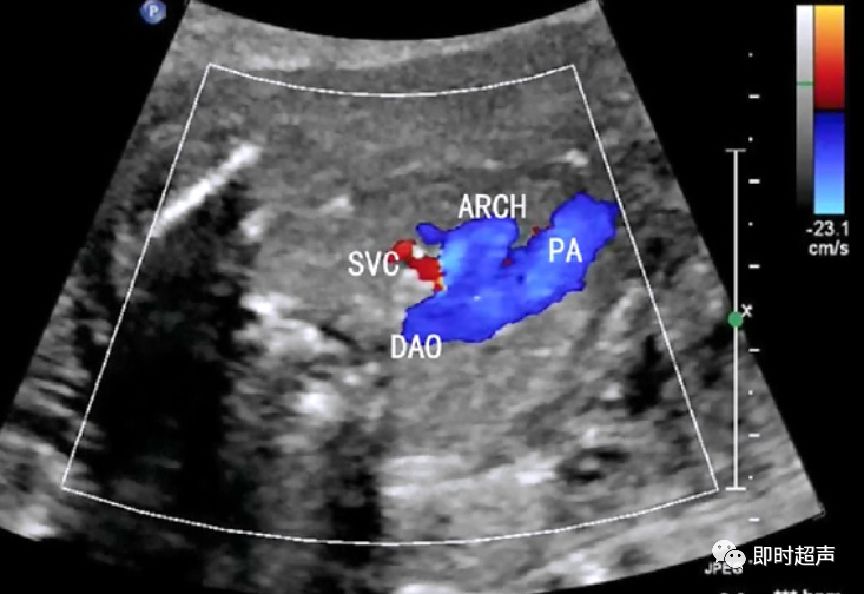

探到胎儿四腔心后,探头稍向胎儿头侧偏移即可显示三血管-气管切面,正常三血管-气管平面从左到右依次显示:肺动脉、主动脉弓、气管、上腔静脉。

- 从左到右依次是肺动脉、主动脉弓和上腔静脉

- 内径从左到右依次递减

- 主动脉弓位于气管的左侧

- 肺动脉和主动脉弓血流都流向脊柱,呈后向血流

- 肺动脉经动脉导管与主动脉弓共同汇入降主动脉